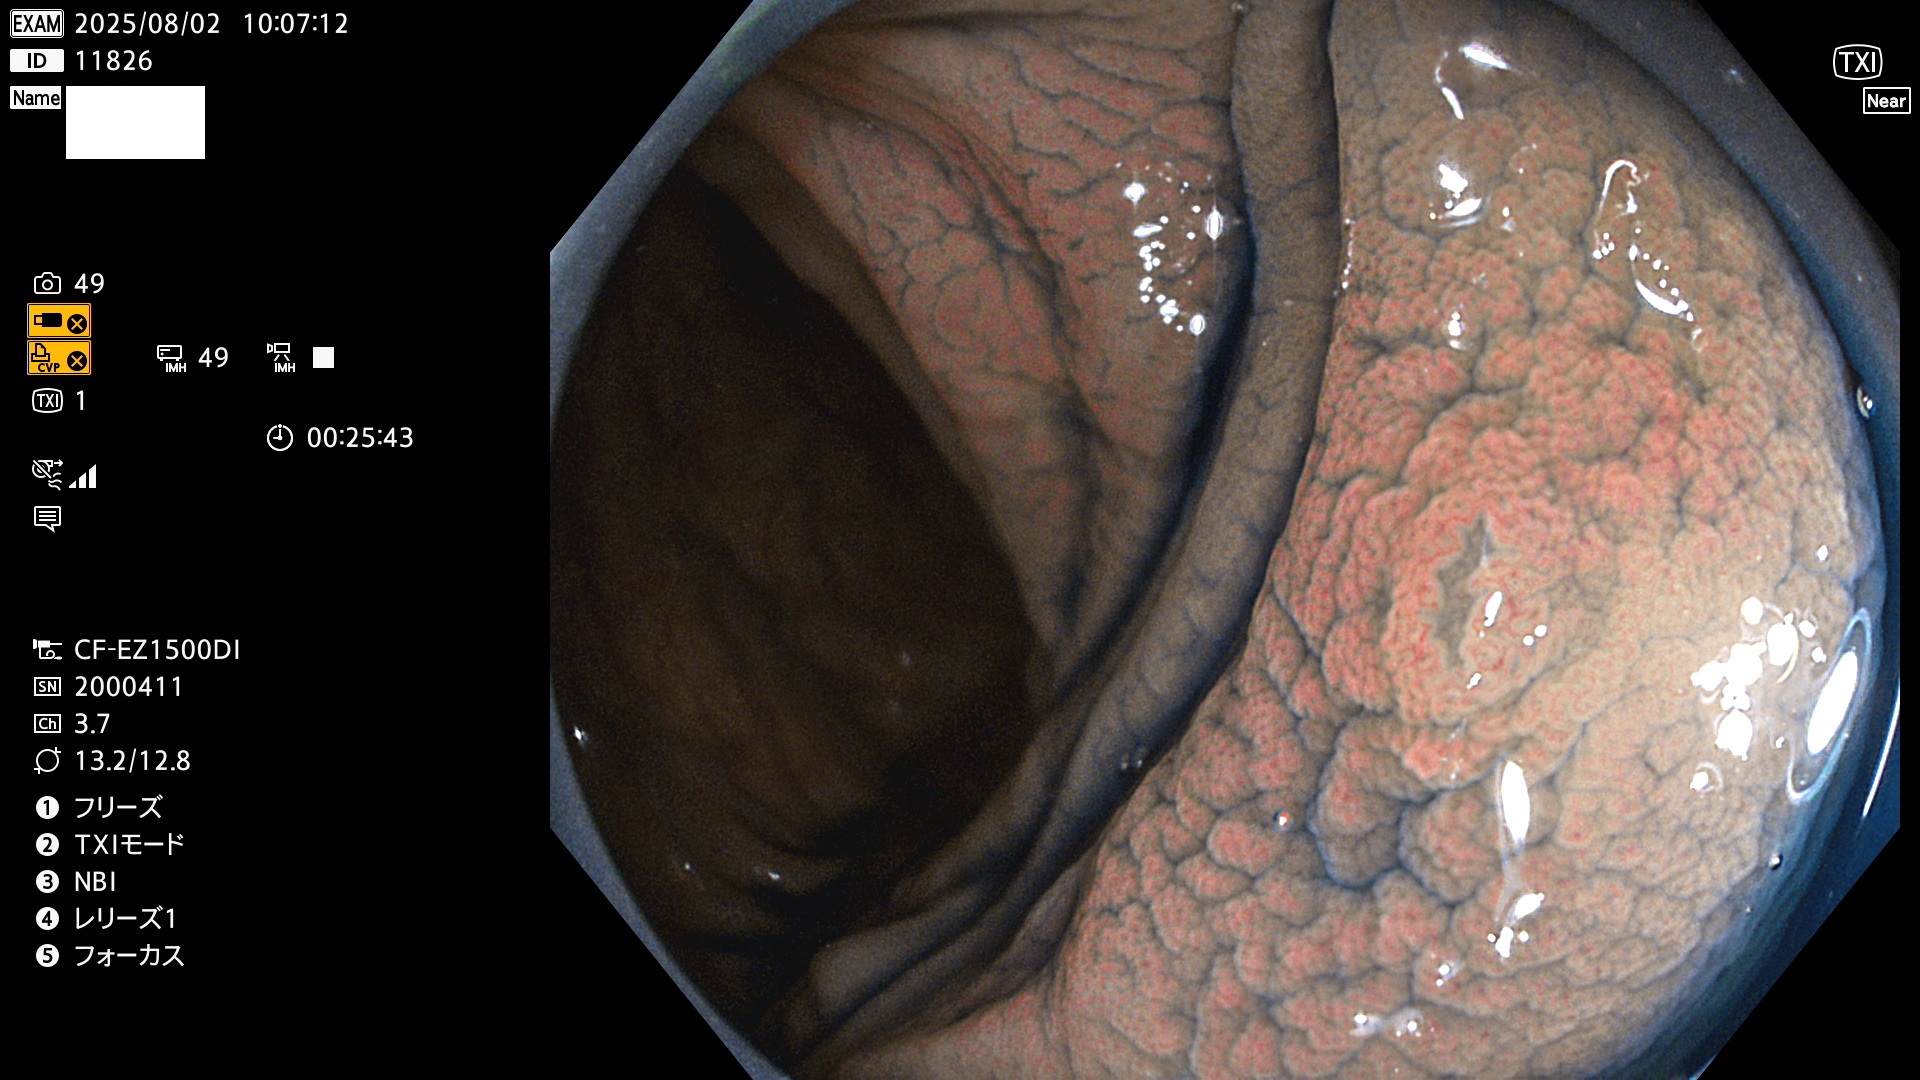

2025年7月31日〜8月3日の4日間(35件)5個 (Uc_ADR=5個/35人=14%)